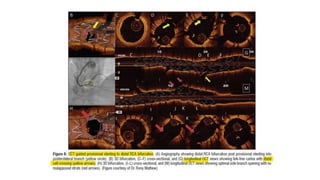

Mechanical catheters (OptiCross IVUS catheter) Solid-state catheter design (Eagle Eye Catheter)

The higher central frequency with mechanical system offers

better resolution and high-quality images aiding clinical

decision-making.

The longer monorail segment provides better trackability to

the solid-state catheter in complex coronary anatomy.

the central location of the guidewire port eliminates the

guidewire artifact

the transducer is house at 25 mm from the tip, which makes it

unsuitable for CTO imaging

the shorter distance from the catheter tip to the transducer (10

mm in Eagle Eye Platinum and 2.5 mm in Eagle Eye

Platinum ST IVUS Catheter; Volcano) offers advantage in

chronic total occlusion (CTO) intervention.

the outer sheath allows precise and controlled

pullback for length and volume assessment.

the catheter does not have outer sheath so that no air trapping

is present around the catheter and it does not need saline

flushing.

hindrance to the rotation of the transducer produces NURD,

and the air trapping in the sheath distorts the image quality

and needs frequent saline flushing

No rotating elements are present in the catheter and hence

nonuniform rotational deformity (NURD) does

not occur with solid-state catheter system.